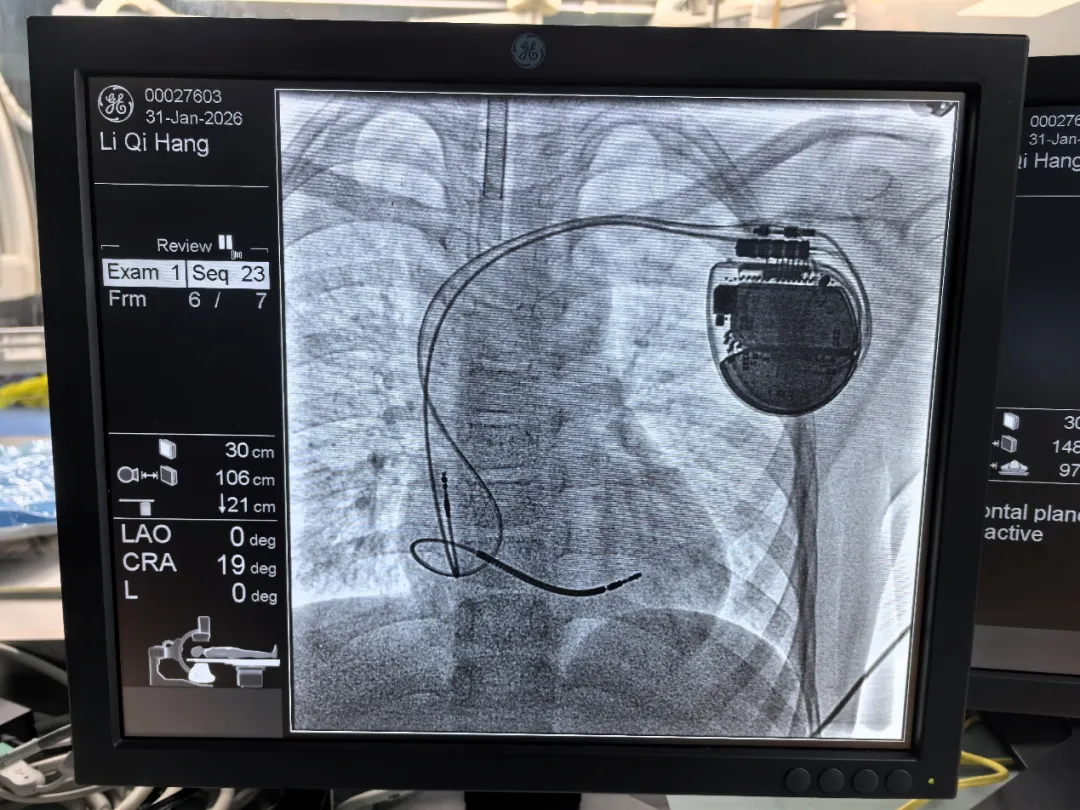

我院心血管内科安新江主任团队在多方位精准评估张同学的病情后,为他安装一款新型的双腔植入型心律转复律除颤器(ICD),手术进行1小时余就顺利完成,当发生危险心电事件时,这款机器可以第一时间除颤,避免了心脏骤停的风险。传统的除颤器安装后,可能无法进行MR的检查,但新型ICD不仅体型小巧,而且可以兼容3.0T全身核磁共振,家长不用担心以后其他疾病的诊治。